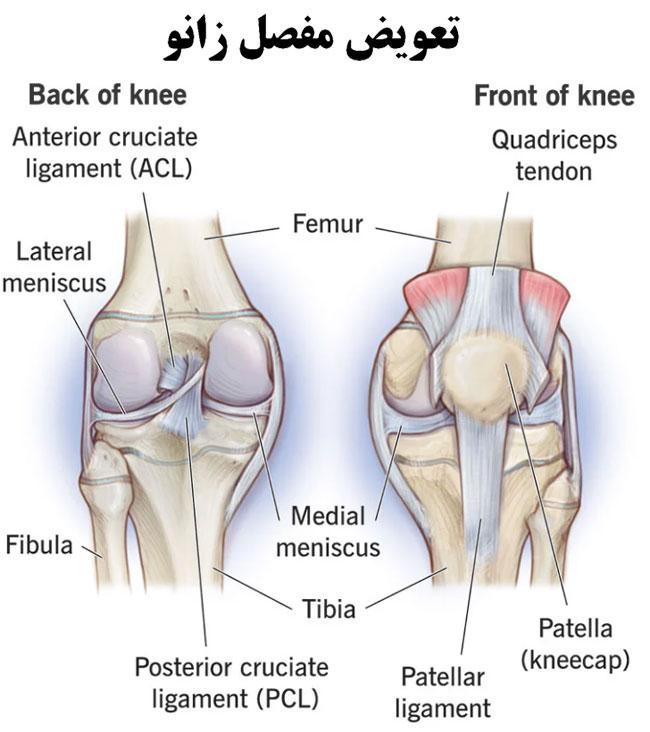

مفصل زانو یکی از پیچیدهترین و مهمترین مفاصل بدن است که تحت تأثیر فشار و استفاده روزانه قرار میگیرد. این مفصل به عنوان یک مفصل قابل حرکت، امکان انجام حرکات پیچیده را به پا ارائه میدهد. برای درک بهتر از ساختار آن، اجزای تشکیلدهنده مفصل زانو را میتوان به شرح زیر بیان کرد:

1. استخوانها: مفصل زانو از سه استخوان اصلی تشکیل شده است:

– استخوان ران (فمور)

– استخوان ساق (تیبیا)

– استخوان کشسان (فیبولا)

2. غضروف:

در این مفصل، بین سطوح استخوانی ران و ساق، غضروفهایی به نام غضروف فمورال و غضروف تیبیال قرار دارد. این غضروفها به عنوان یک لایه ملایم و لغزنده بین استخوانها عمل میکنند و شوک را جذب کرده و فشار روی استخوانها را کاهش میدهند.

3. کیسههای زانویی: مفصل زانو دارای دو کیسه موسوم به کیسههای زانویی است. این کیسهها کیسه زانویی داخلی (منیسکوسها) و کیسه زانویی بیرونی (بورساها) نامیده میشوند. آنها به عنوان محافظ و تسهیلکننده حرکتهای زانو عمل میکنند.

4. رباطها:

در مفصل زانو، چندین رباط نقش مهمی در حفظ استحکام و پایداری مفصل دارند. این رباطها عبارتند از:

– رباط صلیبی قدامی: که از بالای تیبیا به پشت استخوان ران میگسترد و حرکت جلو و عقب را کنترل میکند.

– رباط صلیبی عقب: که از پشت تیبیا به بالای استخوان ران میگسترد و حرکت عقب و جلو را کنترل میکند.

– رباطهای جانبی: شامل رباطهای داخلی و خارجی مفصل زانو هستند که پایداری مفصل را تقویت میکنند.

5. عضلات:

عضلاتی که اطراف مفصل زانو قرار دارند، نقش مهمی در حرکت و پشتیبانی مفصل دارند. عضلات رانی و ساقی مانند عضله رانی (کوادریسپ) و عضلات چهارسر رانی (همسترینگ) تأثیر بسیاری در حرکت و پایداری مفصل زانو دارند.

در کل، مفصل زانو یک سیستم پیچیده است که توسط استخوانها، غضروفها، کیسههای زانویی، رباطها و عضلات تشکیل میشود. همه این اجزا با همکاری به هم میپیوندند تا امکان حرکت نرم و پایداری مفصل را فراهم کنند.